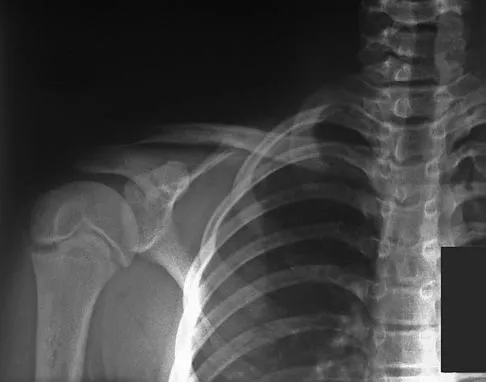

Figure 7 shows the radiograph of an 18-year-old hockey player who sustained a shoulder injury during a fall into the side boards. Examination reveals a significant prominence at the acromioclavicular joint. Management should consist of

Explanation

The radiograph shows a type V acromioclavicular separation with greater than 100% superior elevation of the clavicle. This finding implies detachment of the deltoid and trapezius from the distal clavicle. Because of severe compromise of function and potential compromise to the overlying skin, surgery is the treatment of choice for type V acromioclavicular separations. During reduction and repair, meticulous repair of the deltotrapezial fascia will also aid in securing the repair. Nuber GW, Bowen MK: Acromioclavicular joint injuries and distal clavicle fractures. J Am Acad Orthop Surg 1997;5:11-18.